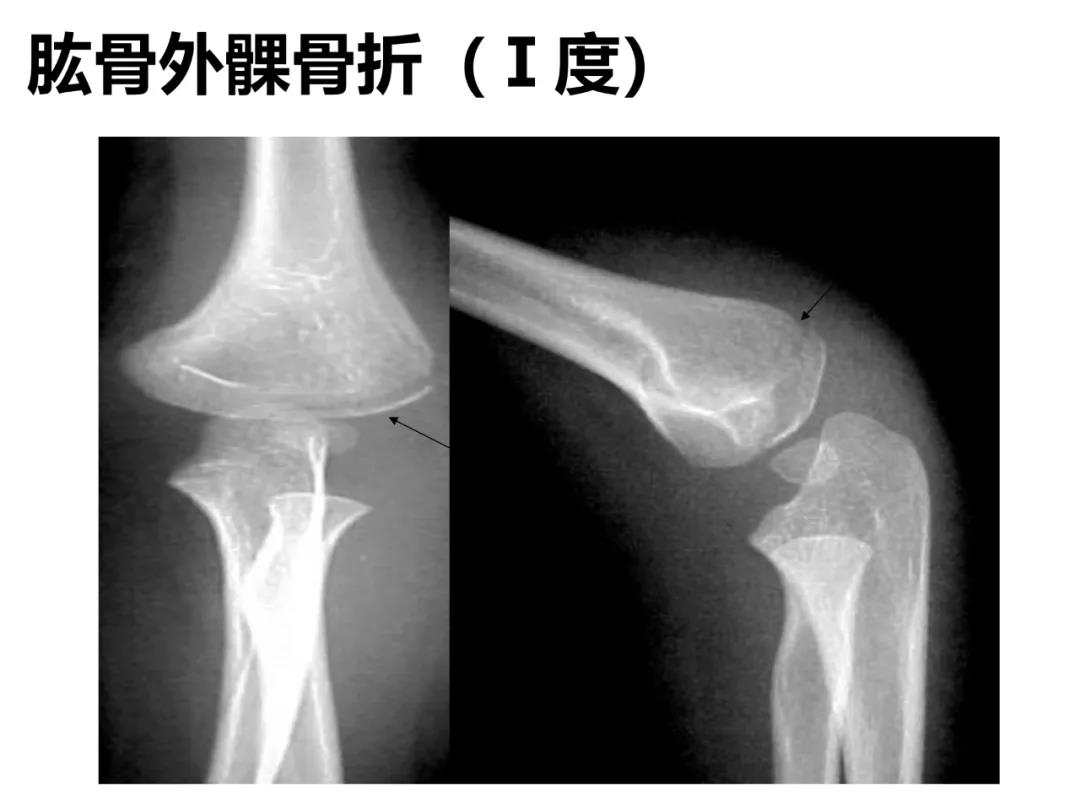

小儿骨科X线片汇总,临床读片宝典!